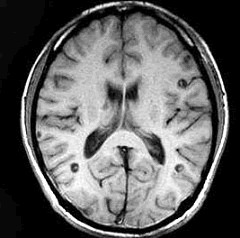

男,29岁。头痛不适半个月。MRI扫描如图示。据此可作出以下最可能的诊断是()

A.脑转移瘤

B.脑囊虫病

C.脑弓形虫病

D.脑脓肿

E.未见异常

[单选题]男,29岁,头痛不适半个月,MRI扫描如图,最可能的诊断是()A.脑转移瘤B.脑囊虫病C.脑弓形虫病D.脑脓肿E.未见异常

[单选题]男,29岁。头痛不适半个月。MRI扫描如图示。据此可作出以下最可能的诊断是()A . 脑转移瘤B . 脑囊虫病C . 脑弓形虫病D . 脑脓肿E . 未见异常

[单选题]男,29岁。头痛不适半个月。MRI扫描如图示。据此可作出以下最可能的诊断是()A .脑转移瘤B .脑囊虫病C .脑弓形虫病D .脑脓肿E .未见异常

男,29岁,头痛不适半个月,MRI扫描如图,最可能的诊断是()

[单选题]男,29岁,头痛不适半个月,MRI扫描如图,最可能的诊断是()A . 脑转移瘤B . 脑囊虫病C . 脑弓形虫病D . 脑脓肿E . 未见异常

男,29岁,头痛不适半个月,MRI扫描如图,最可能的诊断是()

[单选题]男,29岁,头痛不适半个月,MRI扫描如图,最可能的诊断是()A .脑转移瘤B .脑囊虫病C .脑弓形虫病D .脑脓肿E .未见异常